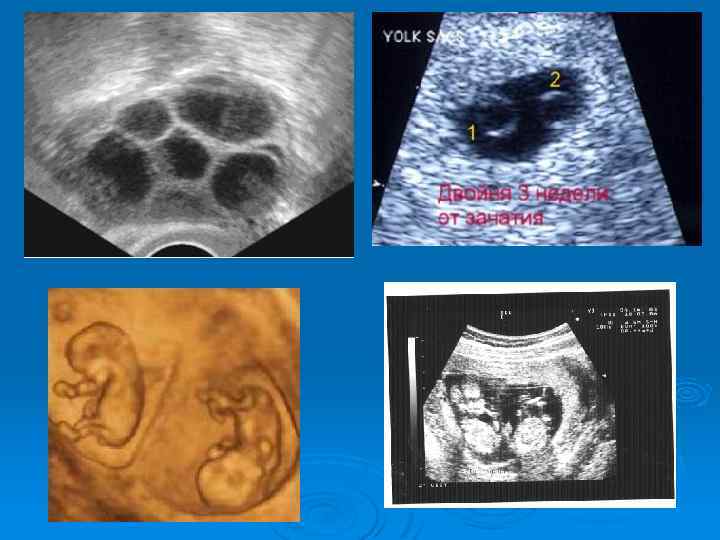

-Достоверные признаки многоплодной беременности выявляются при ультразвуковом исследовании, позволяющем определить многоплодную беременность, начиная с первой ее половины. - Для диагностики многоплодной беременности применяют фоноэлектрокардиографию, при помощи которой можно зарегистрировать сердечные тоны близнецов не только в последние месяцы беременности, но также в срок 20— 22 недели и ранее.